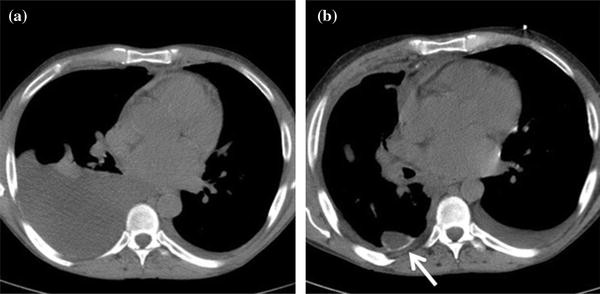

Hầu hết các phương pháp chụp chiếu sẽ giúp chẩn đoán MPE, lượng dịch màng phổi ít nhất 50ml là có thể phát hiện trên phim xquang phổi nghiêng và 200ml dịch là có thể thấy trên phim xquang phổi thẳng. Siêu âm màng phổi qua thành ngực nhạy hơn để phát hiện dịch và di căn màng phổi với dấu hiệu dày màng phổi, các dấu hiệu khác như vách hóa hay dịch khu trú.

Sự có mặt của các nốt màng phổi và các yếu tố khác như nốt cơ hoành hoặc dày màng phổi giúp dự báo ác tính từ 83-100%. Siêu âm màng phổi còn giúp điều trị với xác định vị trí chọc dịch và đặt dẫn lưu. Sau khi chọc hút, siêu âm còn giúp đánh giá khả năng giãn nở của phổi và tình trạng tràn khí màng phổi. Chụp CT ngực rất chính xác phát hiện MPE, đánh giá các thông tin về phổi, màng phổi dày>1cm, nốt màng phổi, dịch khu trú và các dấu hiệu ác tính khác.